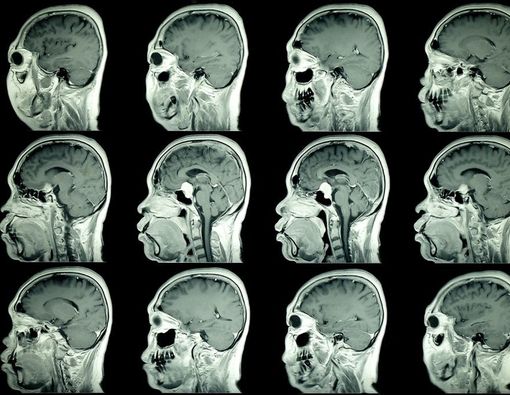

Pengobatan yang diberikan kepada pasien kanker otak berbeda-beda. Pengobatan akan ditentukan oleh dokter berdasarkan jenis, ukuran, dan letak tumor ganas penyebab kanker.

Pada pengobatan kanker otak, dokter dapat melakukan operasi kraniotomi. Kraniotomi dilakukan dengan membuka tengkorak kepala untuk mengangkat sebagian atau seluruh tumor.

Cara ini bertujuan menghilangkan kanker, memperlambat pertumbuhan sel kanker, dan meminimalkan gejala kanker otak.